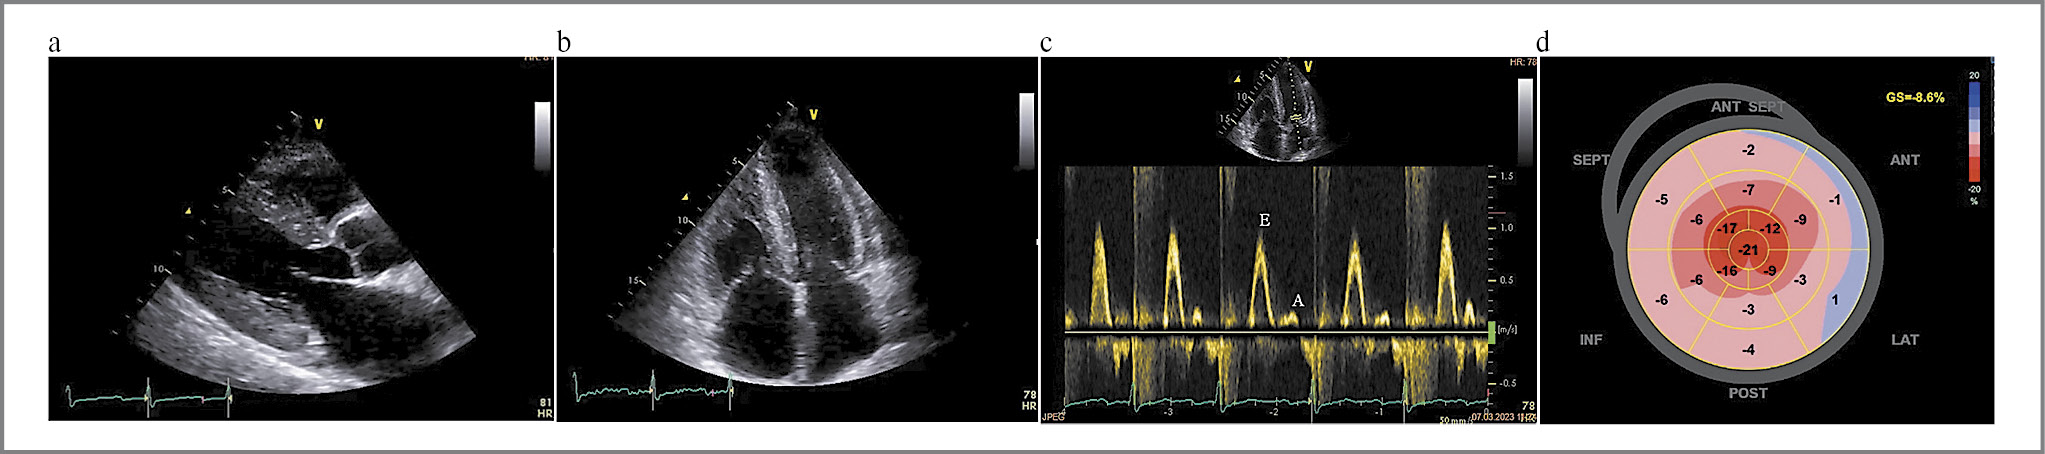

Поражение клапанов достоверно чаще встречалось у пациентов с ATTR-амилоидозом. При детальном анализе подгруппы определялось преимущественно изолированное поражение аортального клапана в виде стеноза устья аорты при ATTRwt-типе и сочетанное поражение митрального и трикуспидального клапанов с формированием тяжелой недостаточности у пациентов ATTRh-типа (рис. 7).

Рис. 7. Клинический пример 2. Пациентка Х. с ATTRh-амилоидозом фенотипа ГФ+РФ+ФВ<50% и поражением клапанов сердца: a–d – выраженное утолщение стенок миокарда ЛЖ и ПЖ, нарушение диастолической функции миокарда ЛЖ по рестриктивному типу (E/A>2), утолщение створок митрального и трикуспидального клапанов, типичный паттерн нарушения глобальной продольной деформации ЛЖ, ФВ ЛЖ 42%.

Fig. 7. Clinical case 2. Patient X. with ATTRh-amyloidosis of the HP+RP+EF<50% phenotype and heart valve involvement: a–d – pronounced thickening of LV and RV walls, restrictive impairment of LV diastolic function (E/A>2), thickening of the mitral and tricuspid valve leaflets, a typical pattern of impaired LV global longitudinal strain, LV EF 42%.

Кроме того, у пациентов с ATTRh-амилоидозом и фенотипом ГФ+РФ достоверно чаще присутствовало поражение митрального и трикуспидального клапанов с формированием тяжелой недостаточности – это можно объяснить тем, что более длительное прогрессирование заболевания в сравнении с AL-амилоидозом позволяет амилоиду медленно откладываться на клапанах сердца и подклапанных структурах, что приводит к их дисфункции [22].